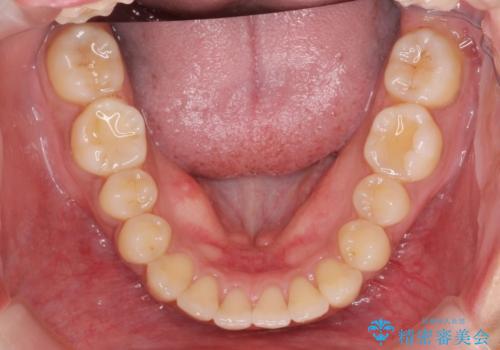

- 長年気になっていた前歯のがたつきをマウスピース矯正で治したい!と希望され来院されました。

奥歯の噛み合わせには問題がなく、前歯のがたつきの改善のみで十分に審美的な結果が得られるため、ワイヤーではなくマウスピース矯正での治療を計画します。

しっかりと前歯のがたつきは改善し見た目が大きく良くすることができました。